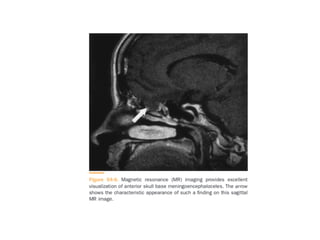

MRI:

• Thin-section MR cisternography is performed with heavily T2-weight

• The intrathecal injection of 0.5 ml of gadopentetate dimeglumine,

diluted in 3-5 ml of CSF, for MR cisternography has been found to

have high sensitivity and specificity for detection of active CSF

rhinorrhea.

• Although prone position is uncomfortable, it may improve

rhinorrhea detection rate.

• Could demonstrate a defect in the cribriform plate and herniation

of meninges and brain tissue with adjacent CSF into the bone

defect.

• CSF rhinorrhea may be difficult to differentiate from sinusitis on

axial images. fluid-attenuated inversion recovery (FLAIR) imaging is

very helpful in differentiating CSF from non-CSF fluid